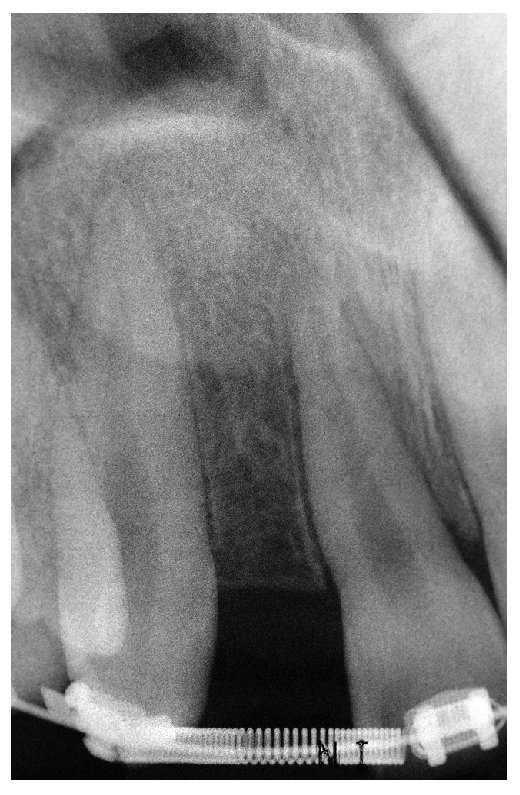

Normalmente, los diagnósticos erróneos tienen como consecuencia medidas terapéuticas erróneas, que posteriormente deben ser corregidas o que son totalmente innecesarias. En el caso presentado en las figuras 1 y 2, tres cirujanos orales distintos diagnostizaron un quiste limitado localmente.

Fig. 1. La radiografía de un paciente a quien debían extraerse los dientes 43 y 44.

Fig. 2. Mediante un tratamiento endodóntico fue posible conservar los dientes naturales; de este modo se revelaron erróneos el diagnóstico inicial y el tratamiento propuesto (tratamiento realizado por el Dr. Paul Bery, Evanston, Illinois, EE. UU.).

La recomendación de tratamiento consistía en extracción y aumento óseo, posiblemente osteodistracción y rehabilitación con implantes y coronas implantosoportadas.

Pese a las posibilidades actualmente disponibles, y debido simplemente a las dimensiones del área afectada, la extracción del canino y de los premolares, la limpieza de la zona curetada quirúrgicamente y la colocación de uno o varios implantes óseos habrían podido conducir a un defecto permanente. Además, incluso con una terapia óptima debe considerarse incierto el pronóstico de los dientes adyacentes. Finalmente, una reevaluación del problema en su conjunto condujo al diagnóstico correcto con el subsiguiente tratamiento exitoso.